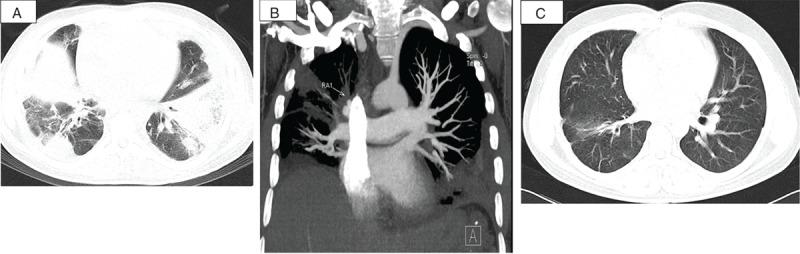

Based on the source of the embolus, septic pulmonary embolism (SPE) can be classified as cardiac, peripheral endogenous, or exogenous. Cardiac SPEs are the most common.We conducted a retrospective analysis of 20 patients with cardiac SPE hospitalized between 1991 and 2013 at a Chinese tertiary referral hospital.The study included 14 males and 6 females with a median age of 38.1 years. Fever (100%), cough (95%), hemoptysis (80%), pleuritic chest pain (80%), heart murmur (80%), and moist rales (75%) were common clinical manifestations. Most patients had a predisposing condition: congenital heart disease (8 patients) and an immunocompromised state (5 patients) were the most common. Staphylococcal (8 patients) and Streptococcal species (4 patients) were the most common causative pathogens. Parenchymal opacities, nodules, cavitations, and pleural effusions were the most common manifestations observed via computed tomography (CT). All patients exhibited significant abnormalities by echocardiography, including 15 patients with right-sided vegetations and 4 with double-sided vegetations. All patients received parenteral antimicrobial therapy as an initial treatment. Fourteen patients received cardiac surgery, and all survived.Among the 6 patients who did not undergo surgery, only 1 survived. Most patients in our cardiac SPE cohort had predisposing conditions. Although most exhibited typical clinical manifestations and radiography, they were nonspecific. For suspected cases of SPE, blood culture, echocardiography, and CT pulmonary angiography (CTPA) are important measures to confirm an early diagnosis. Vigorous early therapy, including appropriate antibiotic treatment and timely cardiac surgery to eradicate the infective source, is critical.